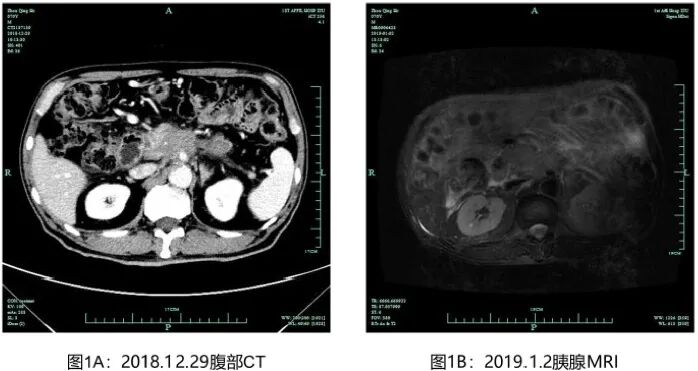

入院后全面检查评估病情:肿瘤标志物CA125 43.2 U/ml、CA199 6297.0 U/ml;肺部CT提示两肺支气管病变、右肺中叶少许炎症、两肺下叶少许间质性改变;胰腺CT平扫+增强提示胰体尾部占位,胰腺癌考虑(图1)。腹腔干及其分支血管、门静脉,脾静脉及肠系膜上静脉受侵,胰源性门脉高压伴侧枝循环开放;肝胆MR平扫弥散+增强提示胰腺颈部、体尾部胰腺癌考虑,侵犯包绕腹腔干动脉及其主要分支、脾动静脉、门脉主干、肠系膜上静脉汇入段,管腔狭窄闭塞;胃周静脉曲张,病灶向腹膜后延伸侵犯。2019-01-02 行B超引导下胰腺肿块穿刺活检(图2),病理提示为(胰腺穿刺)腺癌。

图1 基线影像学评估